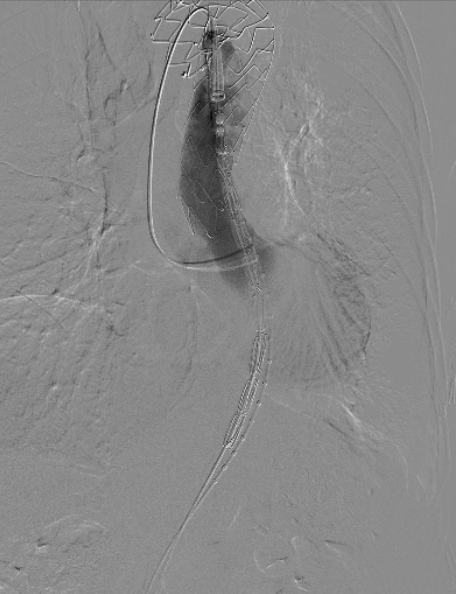

患者平躺后行全麻手术,穿刺双侧股动脉,导入造影导管并进行DSA造影,造影后确认与术前检查结果一致;

治疗车怎么推「弓部重建直通车」鄂尔多斯市中心医院康巴什部介入科运用Castor®分支型支架联合预开窗技术治疗Stanford B型胸主动夹层_https://www.jmylbn.com_新闻资讯_第6张

术前造影